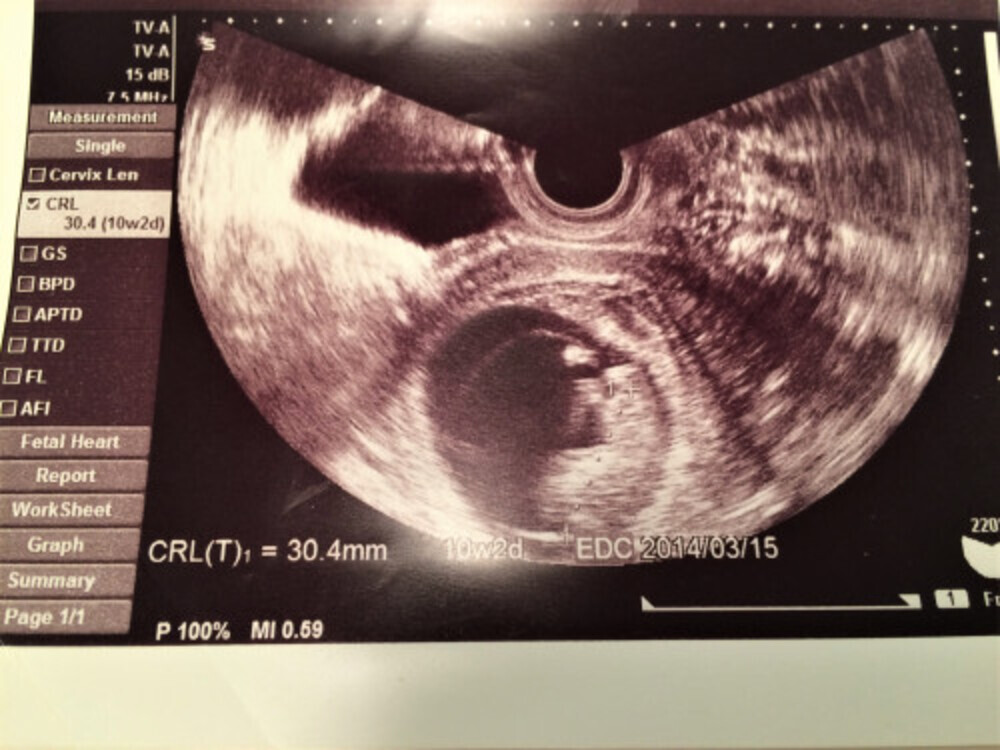

妊娠2ヶ月(4週~7週)赤ちゃんの様子 ・胎芽は胎のう(gs)という袋のなかで成長していきます。最初はおたまじゃくしのような形から徐々に2頭身に。 ・GS6週で15㎝ ・手足のもとができはじめま妊娠2ヶ月(4~7週目)の胎児の発達や妊娠初期症状 妊娠2か月の赤ちゃんは、腕や足が作られ始め、内臓の基礎ができるなど、急激に発達します。 脳や脊髄などの神経細胞もほとんどこの時期につくられます。 お魚のような形をしていた胎芽から、頭と胴 赤ちゃん成長について 19wのときのエコー表示です BPD(頭の幅)425㎝ FL (大腿骨の長さ)254㎝ 1ヶ月後の検診で、 BPD 550㎝ で週数通りでした FL 330㎝ しか成長しておらず2週間ほど成長が遅かったです。 ネットで調べると大腿骨の成長が遅いと障害や